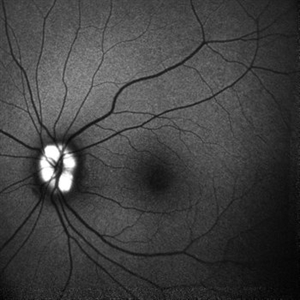

Optic nerve head drusen

Dec 26 2022 by Vaidehi Sathaye

FAF photograph of RE of a 32 year old female with Optic nerve head drusen

Photographer: Dr. Vaidehi Sathaye

Imaging device: Mirante

Condition/keywords: drusen of optic disc